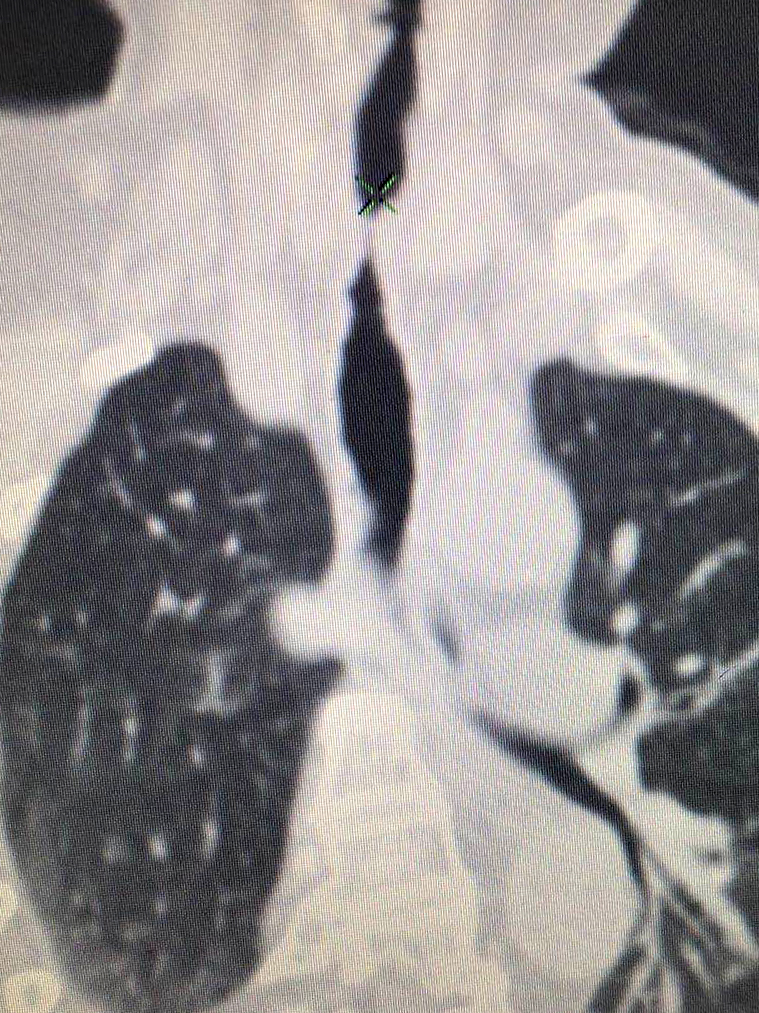

多方打聽下,他們慕名找到我院耳鼻咽喉頭頸外科專家汪文曉?;颊邭夤茏瞠M窄處僅6mm,而正常女性氣管直徑一般為12-15mm,隨時(shí)有窒息的可能??剖覉F(tuán)隊(duì)組織多學(xué)科會(huì)診,商討最優(yōu)治療方案??紤]到患者身體狀況不能接受全麻,最終慎重決定由放射科介入團(tuán)隊(duì)為其施行氣管支架植入術(shù)。

支架植入時(shí),患者的氣管會(huì)被臨時(shí)堵塞,如何冷靜、準(zhǔn)確地在短時(shí)間內(nèi)快速釋放支架,為患者撐起一線生機(jī),術(shù)者的技術(shù)和經(jīng)驗(yàn)至關(guān)重要。同時(shí),該患者氣管狹窄位置較高,若支架植入過低,則不能發(fā)揮效果;若支架植入過高,術(shù)后咽部刺激感明顯,依然不能提高生活質(zhì)量。因此,精確定位支架也是此次手術(shù)的一大難點(diǎn)。